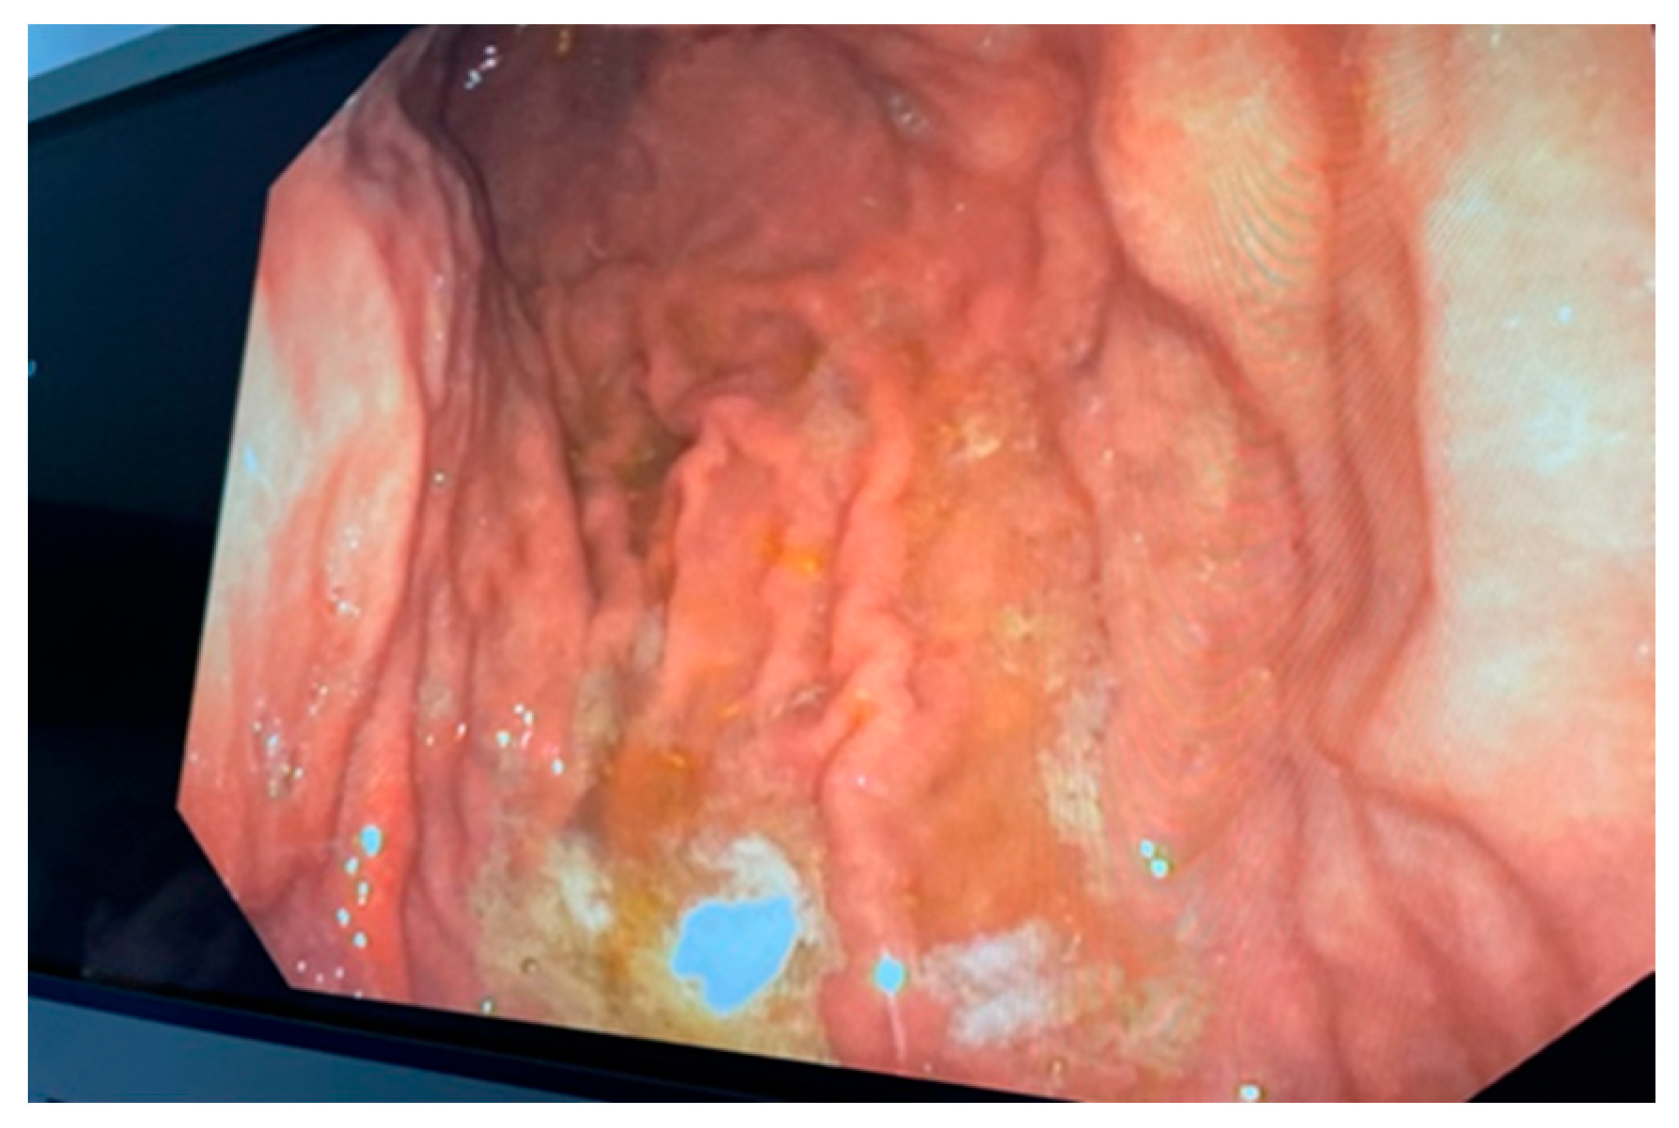

2. Case Report